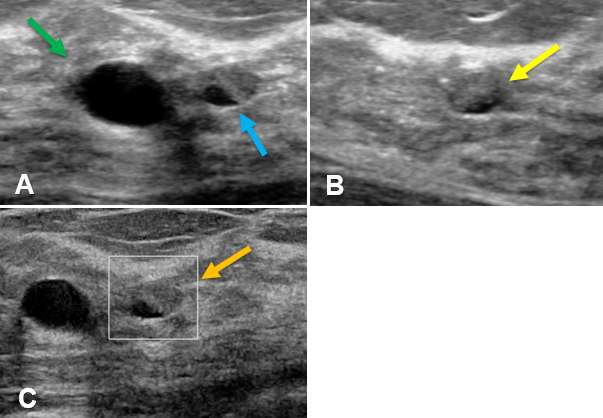

Case: Cysts figure 3

Figure 3A demonstrates a cluster of anechoic sac-like cysts with thin hyperechoic, intervening septa (green arrow). Figure 3B shows the lesion exhibits posterior acoustic enhancement (blue arrow) indicating a fluid-filled lesion. Figure 3C illustrates that the lesion is avascular on color Doppler. Note that the margins of the microcyst are lobular, yet distinct (orange arrows).